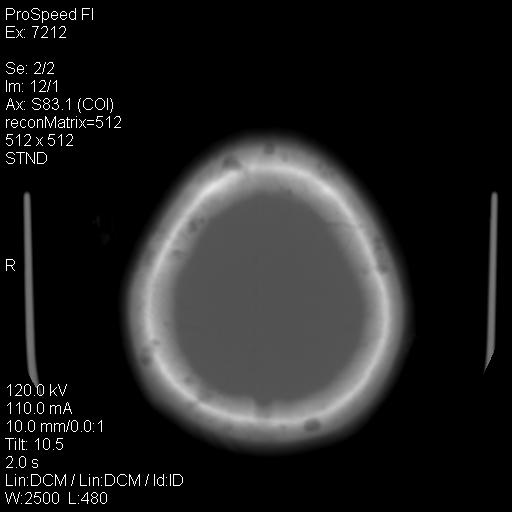

右额叶脑沟变浅,脑表面见新月形稍高密度影,考虑慢性硬膜下出血可能。

额顶骨多发穿凿样骨缺损区,不排除骨髓瘤等改变,进一步检查。

额顶骨多发穿凿样骨缺损区,不排除骨髓瘤或嗜酸性肉牙肿等改变,进一步检查。

1)右侧半卵圆中心腔隙性脑梗塞。2)考虑左侧额部慢性硬膜下血肿(或硬膜下积液)。3)颅骨骨髓瘤不排除;建议行进一步检查。